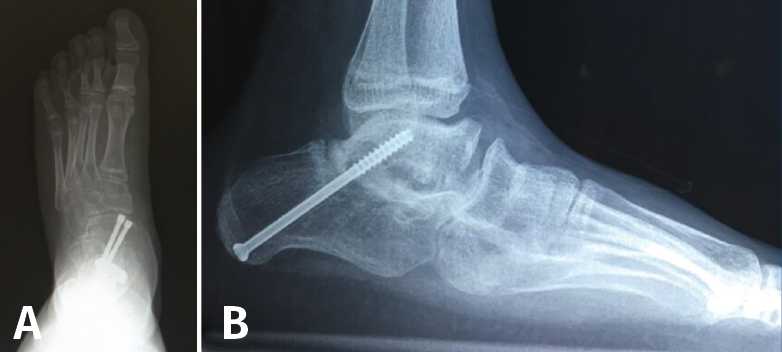

Técnica quirúrgica (Figura 13)

Figura 13. Osteotomía de deslizamiento medial del calcáneo. Escopia intraoperatoria lateral y axial de retropié donde se visualiza la osteotomía de deslizamiento medial del calcáneo.

La osteotomía es perpendicular a la cara lateral del calcáneo y oblicua hacia anterior desde el borde dorsal de la tuberosidad mayor hasta su borde plantar. Aunque clásicamente se realiza esta osteotomía de forma abierta, actualmente se puede realizar de forma percutánea. Mediante maniobra externa realizamos una medialización de al menos 1 cm, más osteosíntesis con AK o tornillos canulados de esponjosa(11).